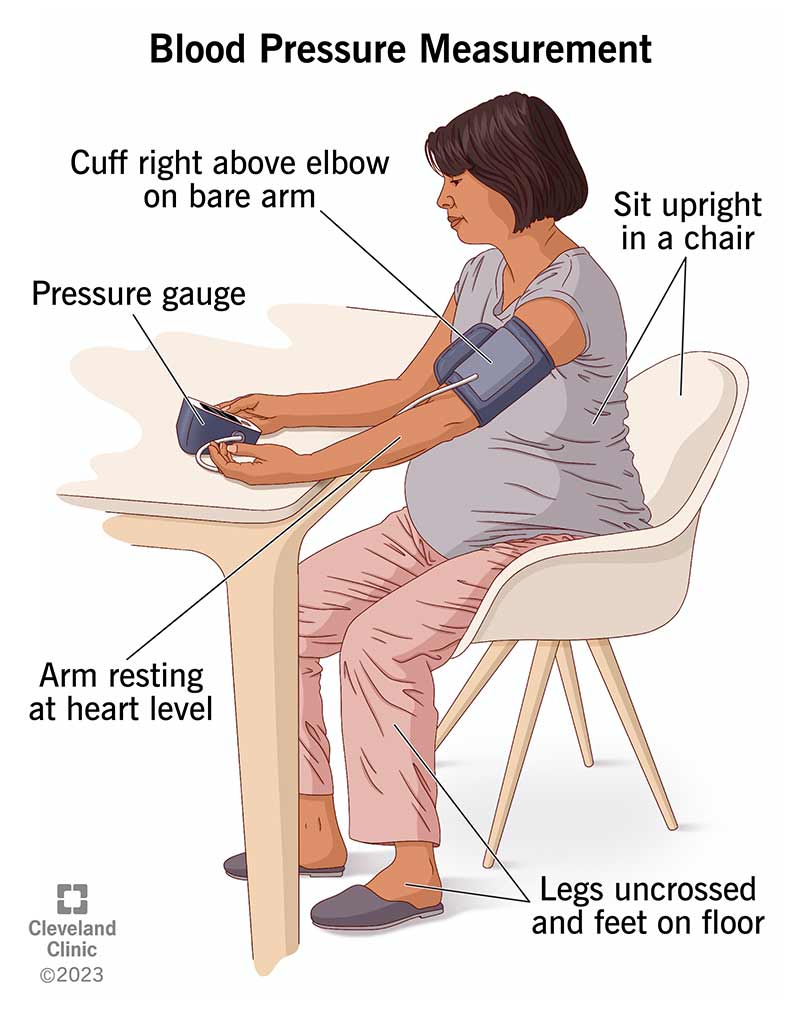

How To Measure Blood Pressure Without Equipment Store

https://my.clevelandclinic.org/-/scassets/images/org/health/articles/25068-blood-pressure-measurement-illustration